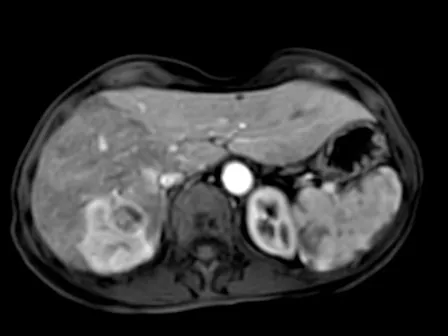

Over the span of three intensive half-days, participants will review and discuss a large selection of CT and MRI liver cases under the guidance of Prof. Giuseppe Brancatelli. Each session starts with short lectures, followed by the live presentation of selected cases, during which participants will be actively involved in describing findings, proposing differential diagnoses, and reaching a final conclusion.

• Interactive case-based learning — explore real-life examples of cystic and solid lesions, incidental findings, and vascular disorders

• Hands-on interpretation — read and analyze individual cases in a guided, step-by-step format